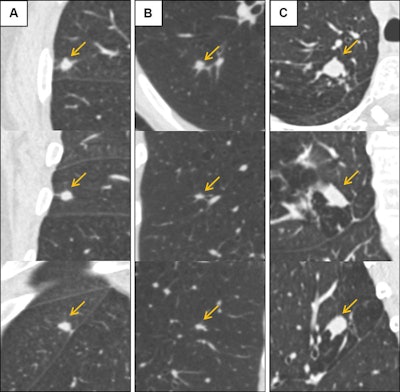

Low-dose CT images show examples of screen-detected pulmonary nodules (arrows) where the deep-learning algorithm provides a more accurate malignancy risk estimation than the Pan-Canadian Early Detection of Lung Cancer (PanCan) model on axial (top), coronal (middle), and sagittal (bottom) planes. (A) Image shows a 9.7-mm malignant nodule (arrows) with a high deep-learning risk score (32.3%) and low PanCan risk score (3.2%) in a 74-year-old male participant diagnosed with squamous cell carcinoma. (B) Image shows a 6.8-mm malignant nodule (arrows) with a high deep-learning risk score (15.9%) and low PanCan risk score (1.2%) in a 71-year-old male participant diagnosed with adenocarcinoma. (C) Image shows a 19 mm benign nodule (arrows) with a low deep-learning risk score (4.7%) and high PanCan risk score (32.7%) in a 50-year-old female participant. Additional PanCan input features used in the model were retrieved from original trial records, as follows: (A) negative for family history of lung cancer, negative for emphysema, negative for spiculation, negative for upper lobe location, nodule count: four; (B) negative for family history of lung cancer, negative for emphysema, negative for spiculation, negative for upper lobe location, nodule count: two; (C) negative for family history of lung cancer, positive for emphysema, negative for spiculation, positive for upper lobe location, nodule count: one. Images and caption courtesy of the RSNA.